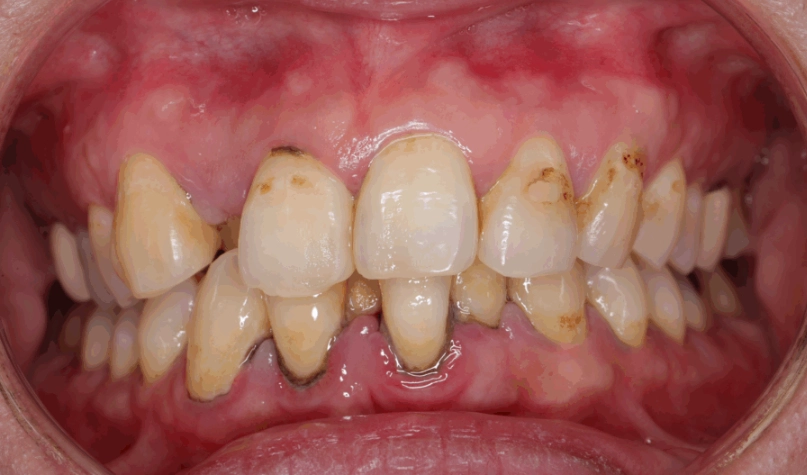

最麻煩的一點是,如果沒有及時清除,牙菌斑裡的細菌會分解食物中的糖分,產生酸性物質。這些酸會腐蝕牙齒琺瑯質,蛀牙就來了。同時,牙菌斑如果堆積在牙齦邊緣,會刺激牙齦發炎,紅腫流血,這就是牙齦炎。再放任下去,發炎往牙根深處走,破壞牙周組織,變成牙周病,牙齒就可能開始搖動。

這是你的終極防線。無論居家清潔多認真,總有一些死角會形成牙結石(鈣化的牙菌斑)。牙結石表面粗糙,會吸附更多牙菌斑,惡性循環。只有牙醫師能用超音波洗牙機將其震除。

| 牙周深層清潔(牙根整平術) | 牙周囊袋內的牙菌斑與結石 | 牙醫師評估後進行 | 治療已形成的牙周病 |